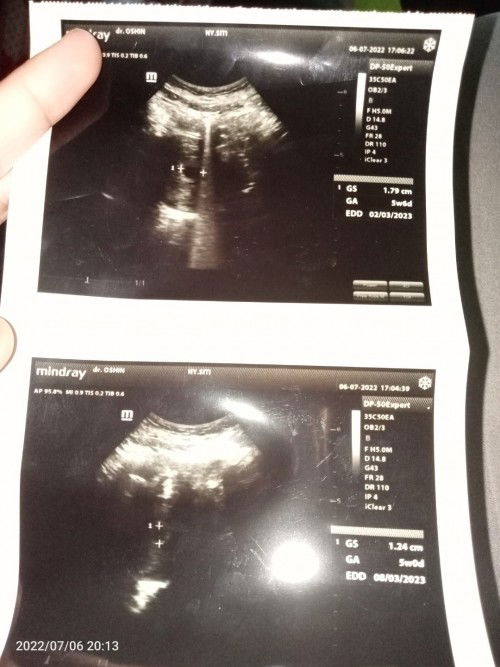

Kehamilanku sudah 9 week tapi hasil USG baru 6 week. Namun itu 2 USG ukuran janin berbeda

itu USG di hari yang sama gak bun? HPHT sama USG pasti beda bun karna kalo USG di lihat dari ukuran janin nya

iya itu USG hari itu juga sama